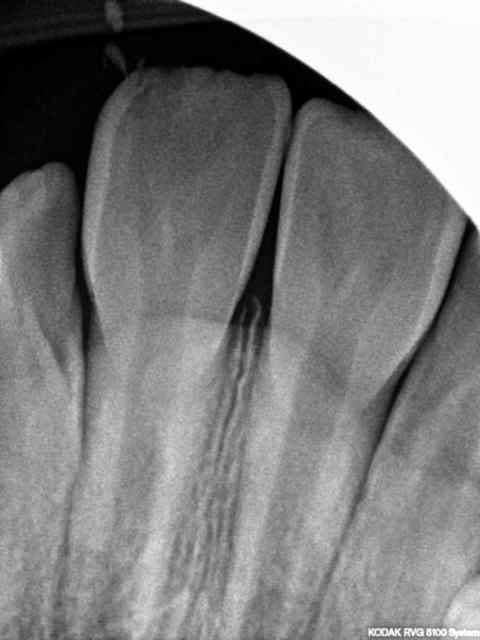

Enfant 8 ans , chute sur des escaliers en béton à l'école , choc sur incisives centrales max. et petite plaie propre lèvre sup. radio de controle: présence de débris(petits) dans la lèvre. cat?